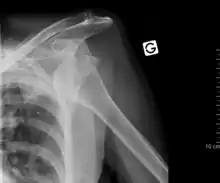

Luxación de hombro

Luxación es la lesión en la cual los segmentos óseos que forman una articulación se separan. La luxación de hombro, o luxación escapulohumeral ocurre con frecuencia debido a la gran amplitud de movimientos que presenta esta articulación. Generalmente es una luxación anterior, es decir la cabeza del húmero se sale de su posición normal en la cavidad glenoidea de la escápula y se coloca delante, haciendo muy difícil y doloroso cualquier tipo de movimiento en el que deban desplazarse estos elementos óseos. Suele ocurrir por un traumatismo, siendo muy frecuente en la práctica deportiva. El tratamiento requiere la colocación mediante maniobras especiales del humero en su lugar correcto, no debe nunca intentar realizarse esta acción por personas que no sean profesionales sanitarios.[2]